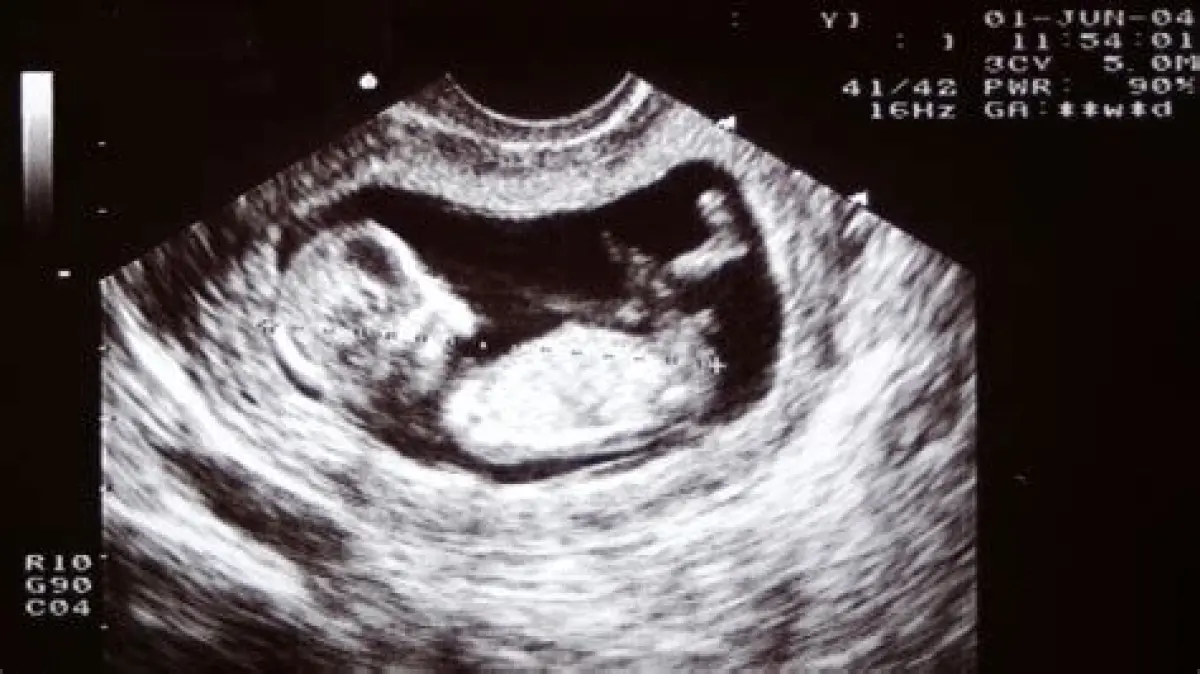

Secara teknis, hamil 2 minggu dihitung dari hari pertama menstruasi terakhir (HPHT). Ini berarti, pada saat itu, pembuahan mungkin belum terjadi. Bahkan jika pembuahan terjadi segera setelah menstruasi selesai, hasil USG belum akan menunjukkan apa pun. Menurut standar umum, kantung kehamilan biasanya baru terlihat melalui USG transvaginal (USG yang dimasukkan melalui vagina) sekitar usia kehamilan 5-6 minggu.

Waktu terbaik untuk melakukan USG pertama kali adalah antara usia kehamilan 6-8 minggu. Pada usia ini, detak jantung janin biasanya sudah bisa dideteksi, dan dokter dapat mengonfirmasi kehamilan yang sehat. Penting diperhatikan, jadwal ini bisa berbeda tergantung pada kondisi medis dan riwayat kehamilan masing-masing individu.